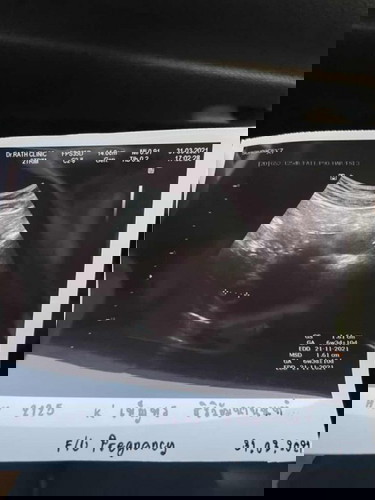

โพสนี้อยากเป็นกำลังใจให้คุณแม่ที่ซาวน์หน้าท้องตอน 6 วีค แล้วยังไม่เจอหัวใจกับตัวอ่อนค่ะ (ภาพแรก) (ภาพสอง) เราไปซาวน์ผ่านช่องคลอดอีกครั้งตอน 8 วีคค่ะ

8 วีค ตัวจิ๋วขนาด 2.6 เซน :)